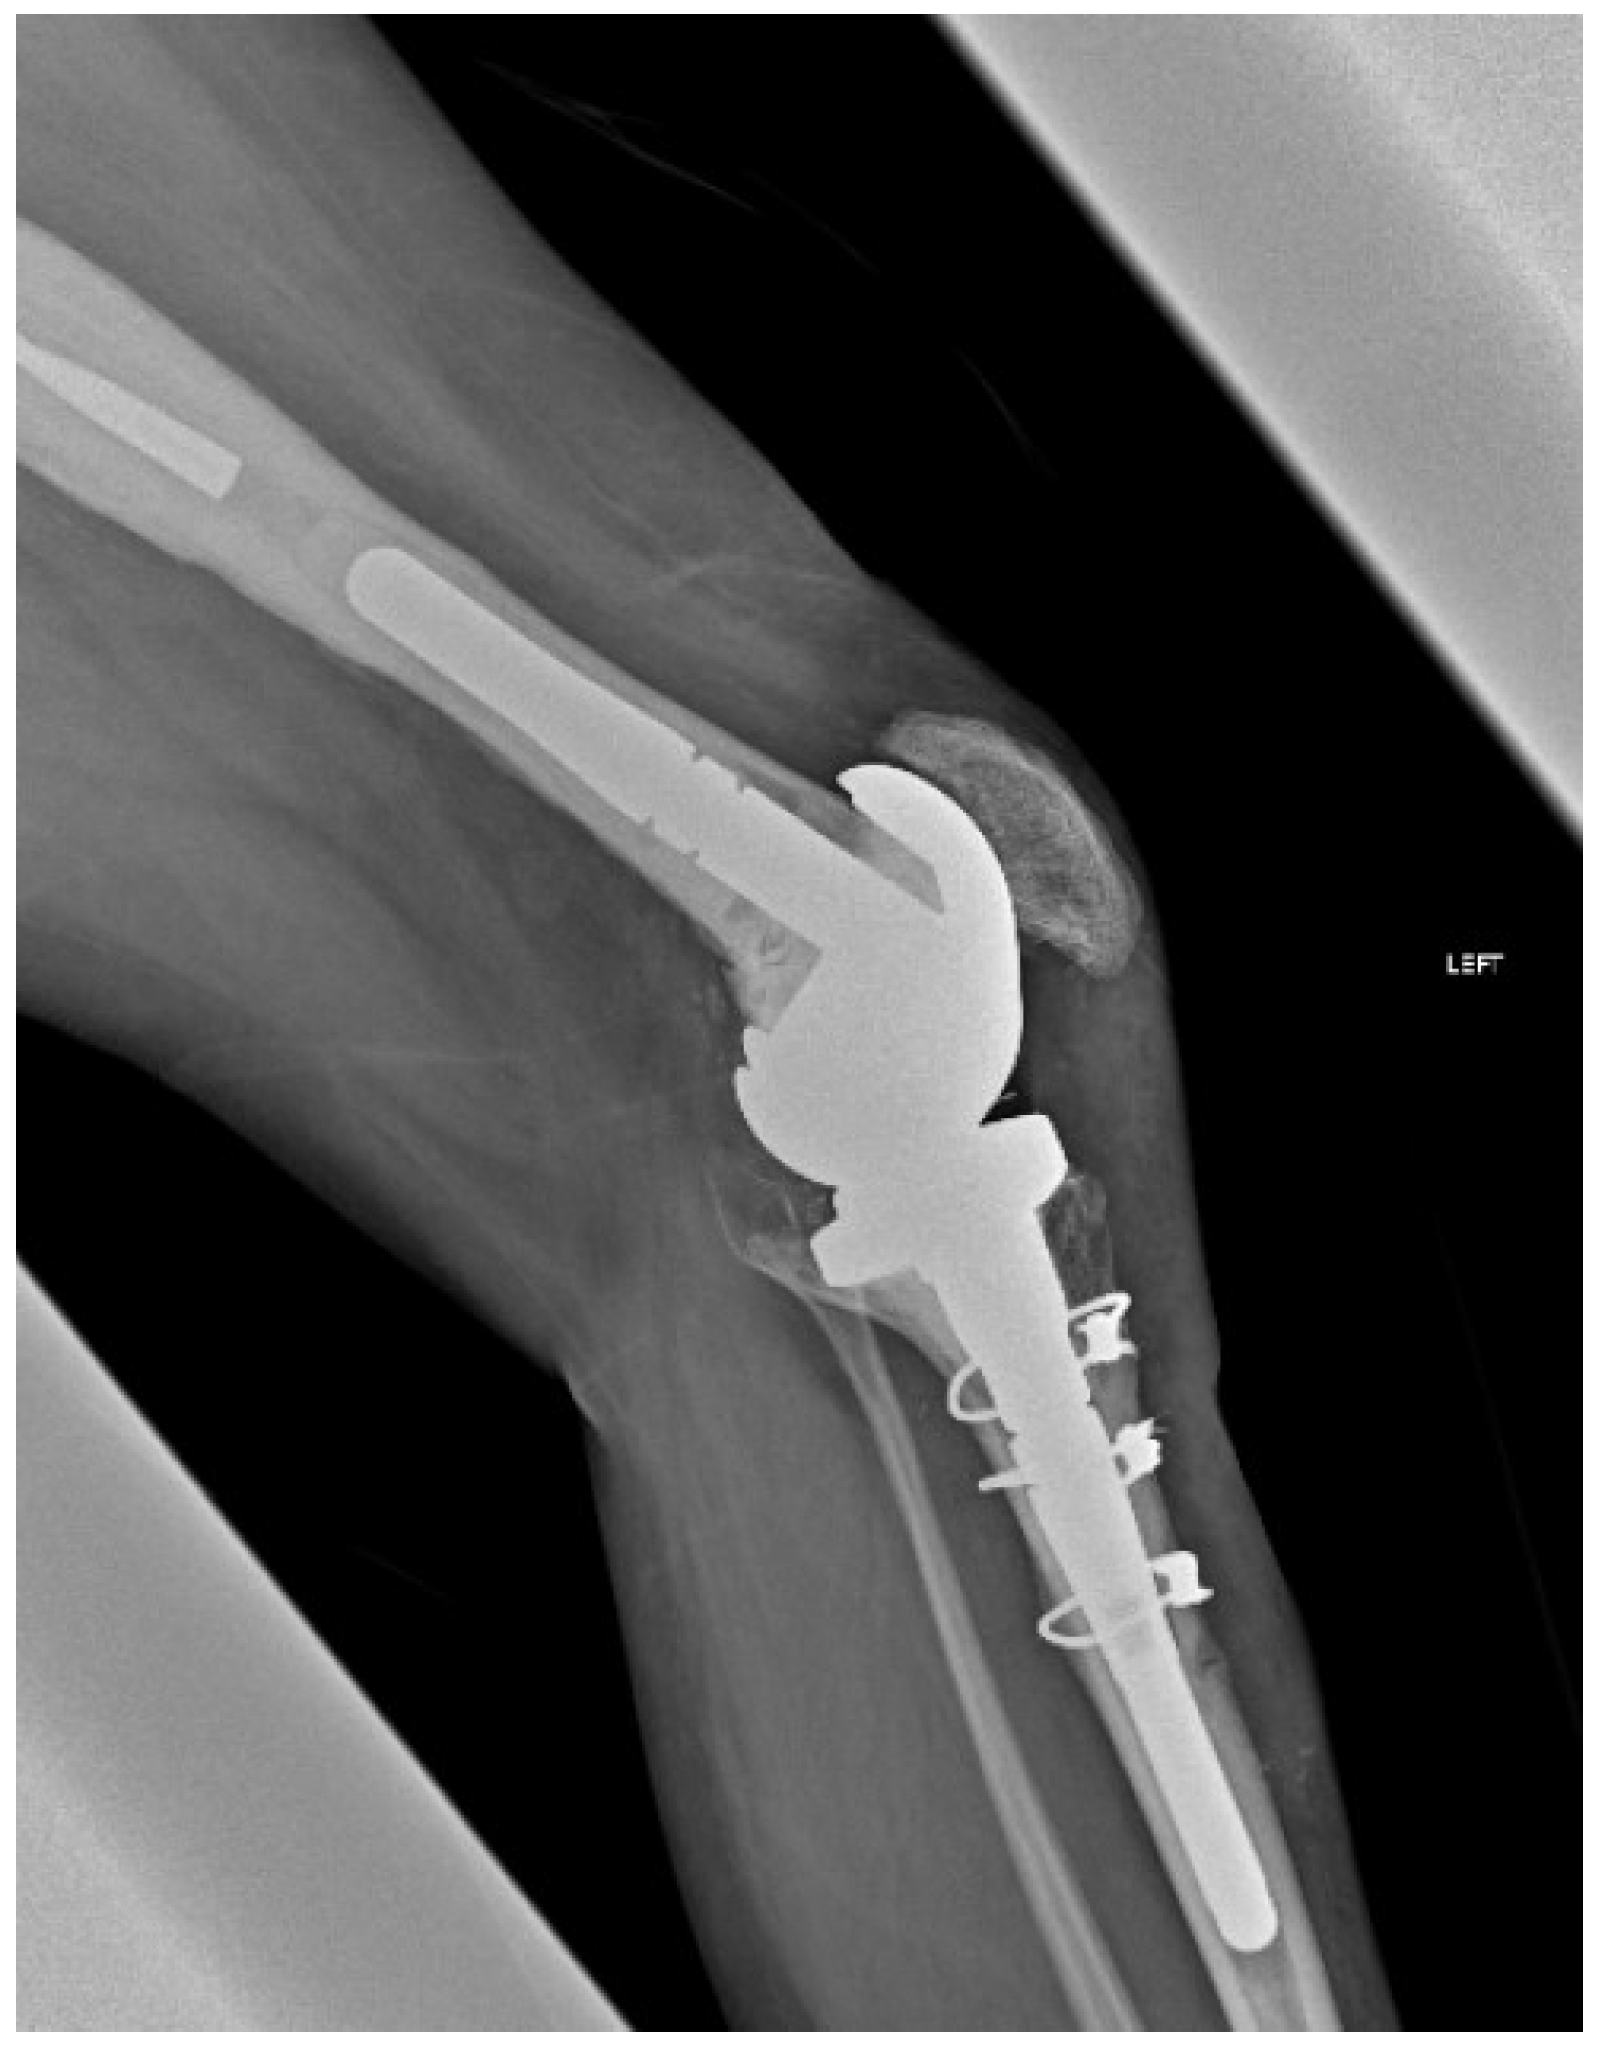

The length of the osteotomy was decided according to the preoperative radiographs and the length of the implant, entirely revealing the tibial stem. The mean length of the osteotomy fragment in our series was approximately 11 cm. The osteotomy was initially marked with the use of a ruler and an electrocautery. The depth of the osteotomy was aimed to be as deep as possible, but while performing ETTO in revision cases with tibial stems, it was limited by the presence of the tibial stem. The stem was then mobilized using osteotomes and pneumatic drills throughout its circumference and was extracted by hitting the baseplate cephalically. After the stem extraction, the intramedullary remaining cement was meticulously removed, usually with the aid of an ultrasound device (Figure 1).

Caution must be given when passing behind the posterior tibia so as not to traumatize the neurovascular bundle. The passer must cross as close as possible to the posterior cortex of the tibia. Afterwards, the tibial component was removed and re-implanted, with bone cement applied solely to the central-metaphyseal region (Figure 3 and Figure 4). Any cement excess was removed from the osteotomy site.

Figure 1. Removal of bone cement from intramedullary canal after the extraction of tibial stem with the use of an ultrasound probe (Case 3).